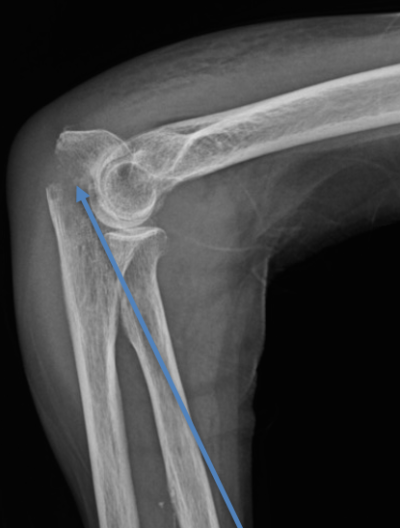

La radiographie réalisée met en évidence la fracture. Un scanner peut être nécessaire pour obtenir une meilleure analyse de la fracture et rechercher d’autres lésions au niveau du coude. En effet, les ligaments et d’autres os peuvent également être atteints lorsque le coude est cassé. Ces blessures peuvent nécessiter une prise en charge également, dans le même temps que le traitement de la fracture de l’os.

Les fractures de l’olécrane peuvent être de différents types allant de la fracture simple jusqu’aux fractures complexes et déplacées de l’articulation du coude.

L’os peut, en plus d’être cassé, être décalé. On parle alors de fracture déplacée.